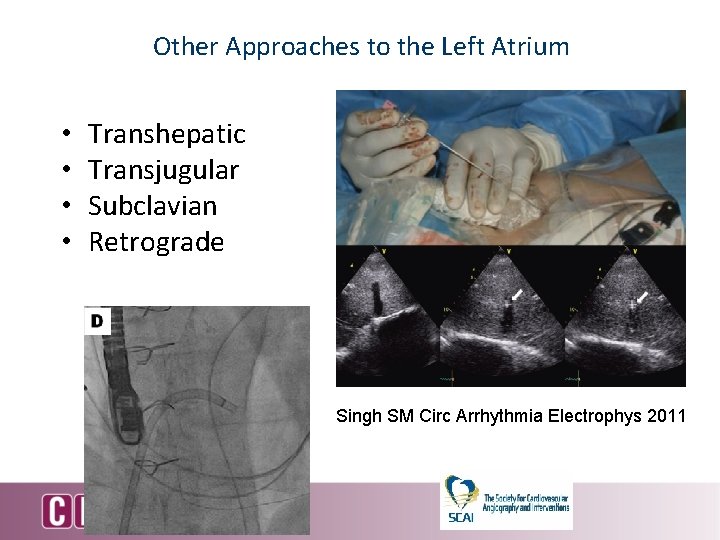

Other Approaches to the Left Atrium • • Transhepatic Transjugular Subclavian Retrograde Singh SM Circ Arrhythmia Electrophys 2011